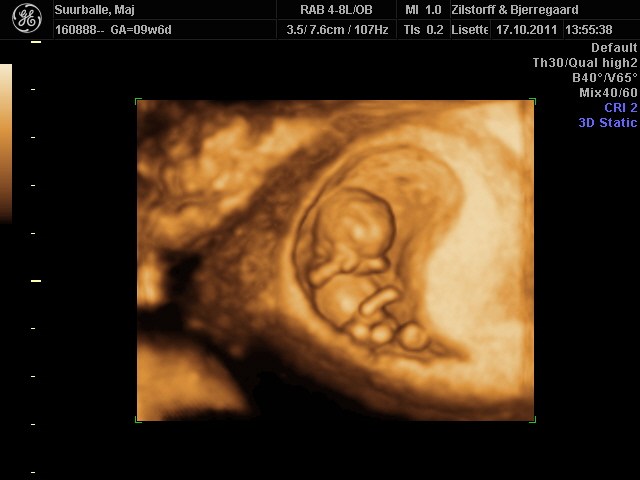

Troede ikke at den var så "levende" allerede.. Den lille fister på knap 3,4 cm sprællede helt vildt jo! Og tænk at den allerede har arme, ben, små øre, noget der ligner øjne, næse...... HELT vildt at opleve <3

Ja, det er det.. Og nu lærte jeg det lige lidt bedre tror jeg...: 4D bruger de til at se bevægelserne.

Og vi fik så både s/h, 3D og 4D